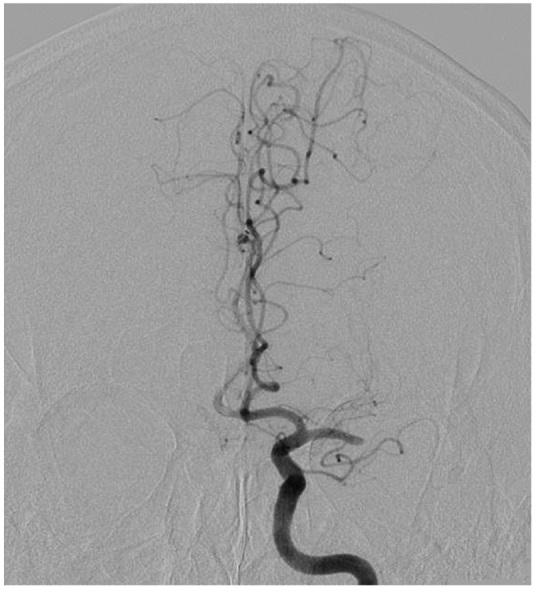

The optional endovascular approach for acute ischemic stroke is unclear. The Trevo stent retriever can be used as first-line treatment for fast mechanical recanalization. The authors developed a treatment protocol for acute ischemic stroke based on the assessment of clot quality during clot removal with the Trevo. This prospective single-center study included all patients admitted for acute ischemic stroke between July 2014 and February 2015, who underwent emergency endovascular treatment. According to the protocol, the Trevo was used for first-line treatment. Immediately after the Trevo was deployed, the stent delivery wire was pushed to open the stent by force (ACAPT technique). Clot quality was assessed on the basis of the perfusion status after deployment of the Trevo; continued occlusion or immediate reopening either reoccluded or maintained after the stent retriever had been in place for 5 min. If there was no obvious clot removal after the first pass with the Trevo, according to the quality of the clot, either a second pass was performed or another endovascular device was selected. Twelve consecutive patients with acute major cerebral artery occlusion were analyzed. Thrombolysis in cerebral infarction score 2b and 3 was achieved in 11 patients (91.7%) and 9 (75%) had a good clinical outcome after 90 days based on a modified Rankin scale score ≤ 2. Symptomatic intracranial hemorrhage occurred in 1 patient (8.3%). The overall mortality rate was 8.3%. Endovascular thrombectomy using the Trevo stent retriever for first-line treatment is feasible and effective.

急性缺血性卒中的选择性血管内治疗方法尚不清楚。Trevo支架取栓器可作为快速机械再通的一线治疗方法。作者基于使用Trevo取栓过程中对血栓质量的评估,制定了一种急性缺血性卒中的治疗方案。这项前瞻性单中心研究纳入了2014年7月至2015年2月期间因急性缺血性卒中入院并接受急诊血管内治疗的所有患者。根据该方案,Trevo被用作一线治疗。在部署Trevo后,立即用力推送支架输送钢丝以打开支架(ACAPT技术)。根据Trevo部署后的灌注状态评估血栓质量;持续闭塞或立即再通,在支架取栓器放置5分钟后要么再次闭塞要么保持通畅。如果使用Trevo首次取栓后没有明显的血栓清除,根据血栓质量,要么进行第二次取栓,要么选择另一种血管内装置。对连续12例急性大脑中动脉闭塞患者进行了分析。11例患者(91.7%)达到脑梗死溶栓评分2b和3分,90天后基于改良Rankin量表评分≤2,9例(75%)患者获得良好的临床结局。1例患者(8.3%)发生有症状性颅内出血。总死亡率为8.3%。使用Trevo支架取栓器进行一线治疗的血管内血栓切除术是可行且有效的。